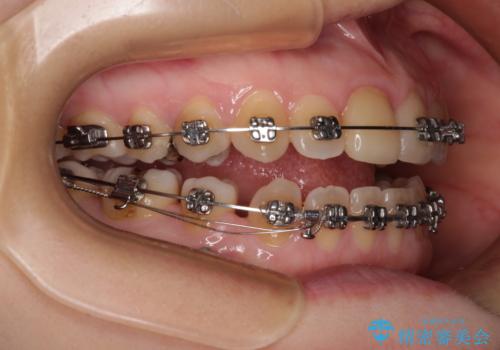

- 矯正装置

- メタルブラケット

マウスピース矯正を検討されていましたが、後戻りの隙間が非常に大きく、奥歯を前方に移動させる必要があるため、ワイヤー装置にて矯正治療を行うこととしました。

舌の突出癖が非常に強く、その影響で隙間ができてしまったので、舌のトレーニングをしっかりと行っていただきました。

上顎歯列は歯の移動量が少なかったため、セラミッククラウンは装置を装着せずに治療を終えることができました。